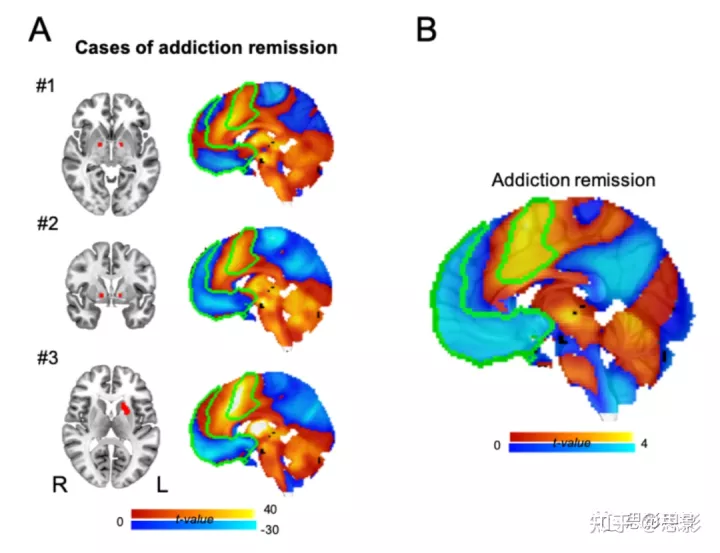

为了研究泛化,我们研究了 186 名完成酗酒风险评估的病变患者。与较低酗酒风险相关的病变与破坏吸烟成瘾的病变表现出相似的连接(图3a和b;空间r=0.65,置换检验P=0.04),即使控制吸烟状况(空间 r=0.69,置换检验 P=0.04)。数据集之间的这种一致性是由网络连接驱动的,而不仅仅是病变位置,因为使用传统 VLSM 重复分析未能显示相似性(空间 r=-0.15,P=0.83)。这种一致性也特定于成瘾风险,因为为其他 10 个明尼苏达多相人格量表(Minnesota Multiphasic Personality Inventory, MMPI)变量生成的地图以及成瘾风险地图(P<0.001)与使用其他神经心理学变量生成的 27 个地图不匹配(图 3c )。我们还确定了3例破坏尼古丁以外物质成瘾的病变病例报告,并发现网络连通性与破坏吸烟成瘾的病变相似(P<0.05;补充材料图 11)。

图 S11:调查结果对其他物质使用障碍的普遍性。

我们确定了破坏多物质成瘾(案例#1)、阿片类药物和酒精成瘾(案例#2),以及对酒精和尼古丁的依赖(案例#3)(A)的脑损伤病例报告。 对于每种情况,我们显示病变位置(左,红色)和与病变位置的连接(右)。绿色覆盖显示了我们成瘾缓解网络中重要区域的轮廓(B,参见图 2D)。 这些连接图中的每一个都更类似于破坏吸烟成瘾的病变的连接图,而不是与不戒烟相关的病变图(Mann-Whitney U-test p < 0.05 在所有情况下)。